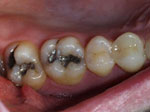

In the images above, the back 2 teeth used to be filled with dark silver fillings and they were replaced with beautiful bonded restorations.